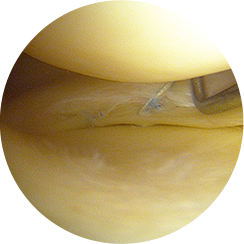

무릎 관절내시경 수술은 1cm 미만의 작은 수술 부위에 내시경과 수술기구를 삽입하여

손상된 연골이나 인대, 이물질 등을 직접 확인하고 정밀하게 치료하는 수술입니다.

관절내시경을 삽입해 내부를 실시간으로 보면서

손상된 부위를 정밀하게 제거하거나 봉합하기 때문에,

CT나 MRI로도 정확히 파악하기 어려운 미세한 연골 손상이나

관절 내부 이상까지 확인하여 보다 정확한 진단과 즉각적인 치료가 가능합니다.

1cm 미만의 절개 부위를 통해

관절내시경을 삽입합니다.

고해상도 영상으로

연골·인대·반월상연골의

손상 부위를 정확히 확인합니다.

특수 미세 기구를 이용해

손상된 부위를 절제하거나,

봉합합니다.